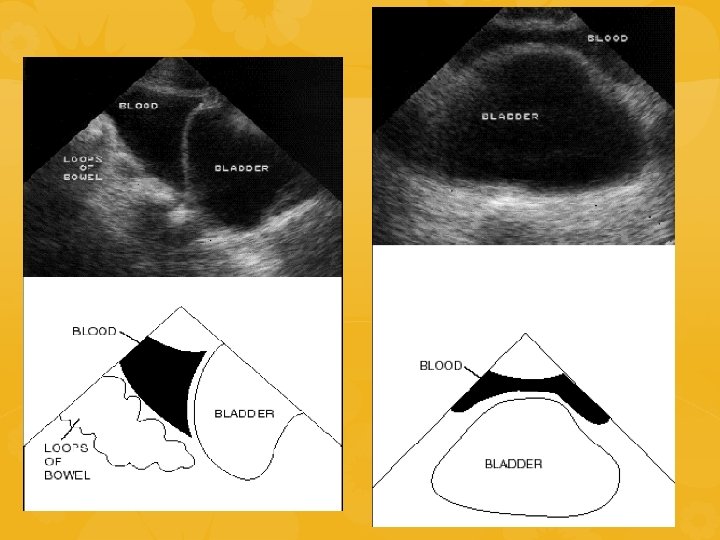

ECOFAST SCOPO: identificare raccolte ematiche nelle cavità del corpo dove non dovrebbe esserci Esplorazione 4 aree 1. QSD 2. Sottoxifoidea 3. QSS 4. Soprapubica INDICAZIONI NEL TRAUMA: • Emorragie toracoaddominali • Trauma penetrante toracoaddominale • Sospetto tamponamento pericardico • Paziente con ipotensione di ndd • Trauma toracoaddominale nella

Finestra soprapubica • • • Intera pelvi esplorabile iniziando con la sonda in posizione trasversa dal fondo e poi in posizione sagittale Scavo del Douglas: porzione più declive della cavità peritoneale Primo segno di presenza di sangue libero: 2 piccoli triangoli ai due lati del retto